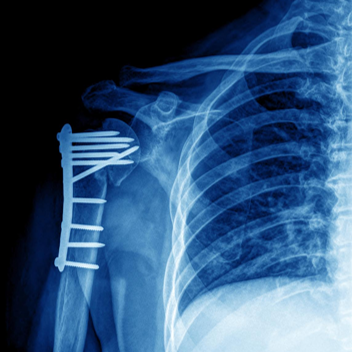

钢板和螺钉固定

A.锁骨骨折, B.前方钢板固定

双微型碎片钢板

锁骨骨折的切开复位内固定